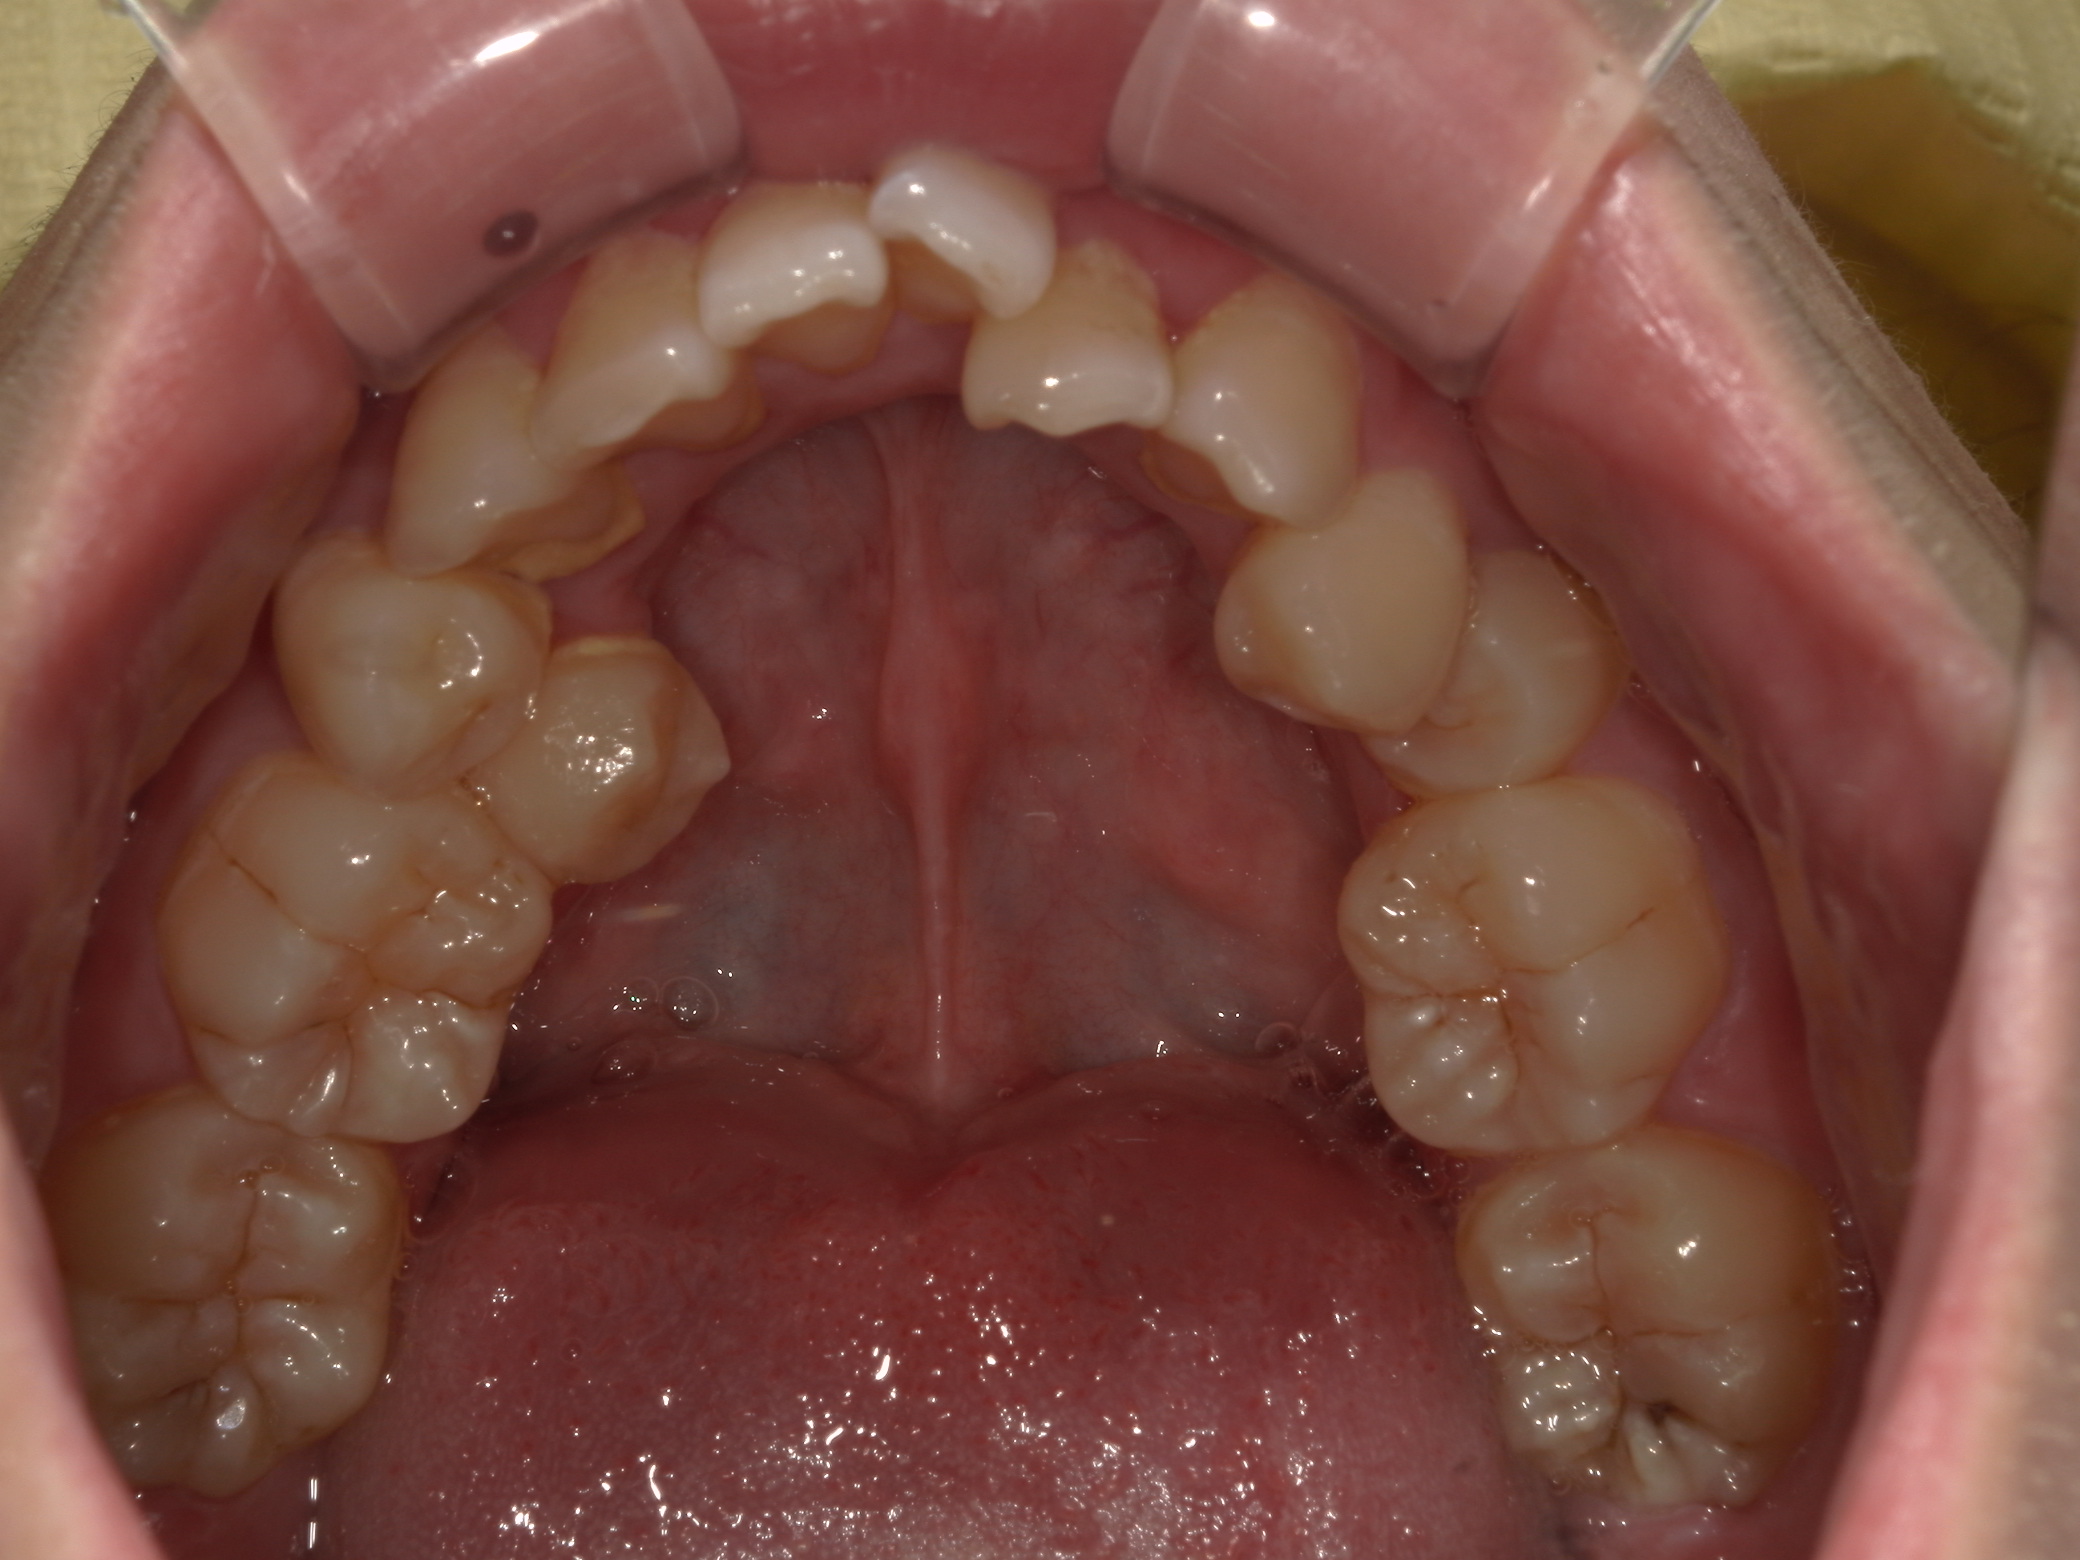

歯並び・かみ合わせ・口元の見た目が気になる

| 年齢・性別 | – |

|---|---|

| 主訴 | 歯並び・かみ合わせ・口元の見た目が気になるとの事でご相談があり矯正の治療を行いました。 |

| 治療期間・回数 | 2年 |

| 費用 | 1,001,000円 |